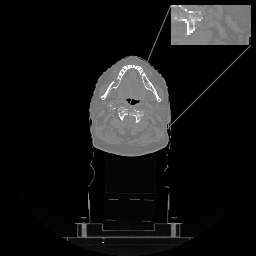

Secondly, to further investigate the generalization behaviour of LIRE+, we report the results of the finetuning experiment in Table 4. Interestingly, after identical finetuning, both full LIRE+ and LIRE+ with only 9 iterations demonstrate substantially better performance compared to LIRE and \partialU-net. The better generalization of LIRE+ after finetuning on a limited amount of data is in agreement with the lower parameter count of the new model. Axial image slices from finetuned HN models are provided in Figure 7, where HU range is set to (-1000, 1000).

Refer to caption

(a)

(b)

(c)

(d)

Figure 7: (a) Axial slice of HN CT, HU range=(-1000, 1000), (b) \partialU-net, (c) LIRE, and (d) LIRE+ 12 it.